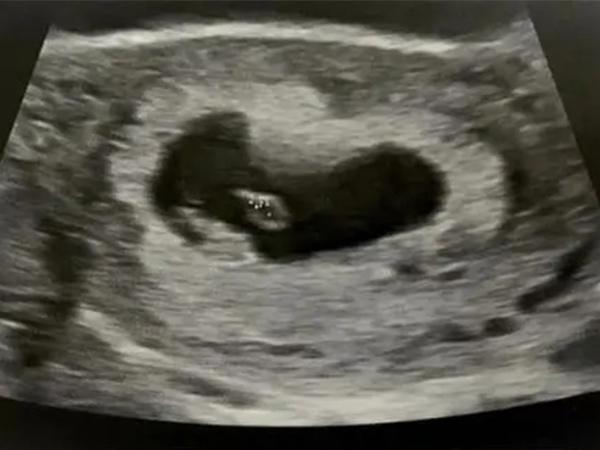

详解双胞胎卵黄囊出现时间,超过孕8周仍不可见一定不正常

卵黄囊是位于孕囊内部的胚胎组织形式,会随着胚胎的发育逐渐出现,然后又随着胚胎的发育逐渐变小,直至被吸收消失。而卵黄囊出现的时间一般是在4周左右,但是做B超被发现的..